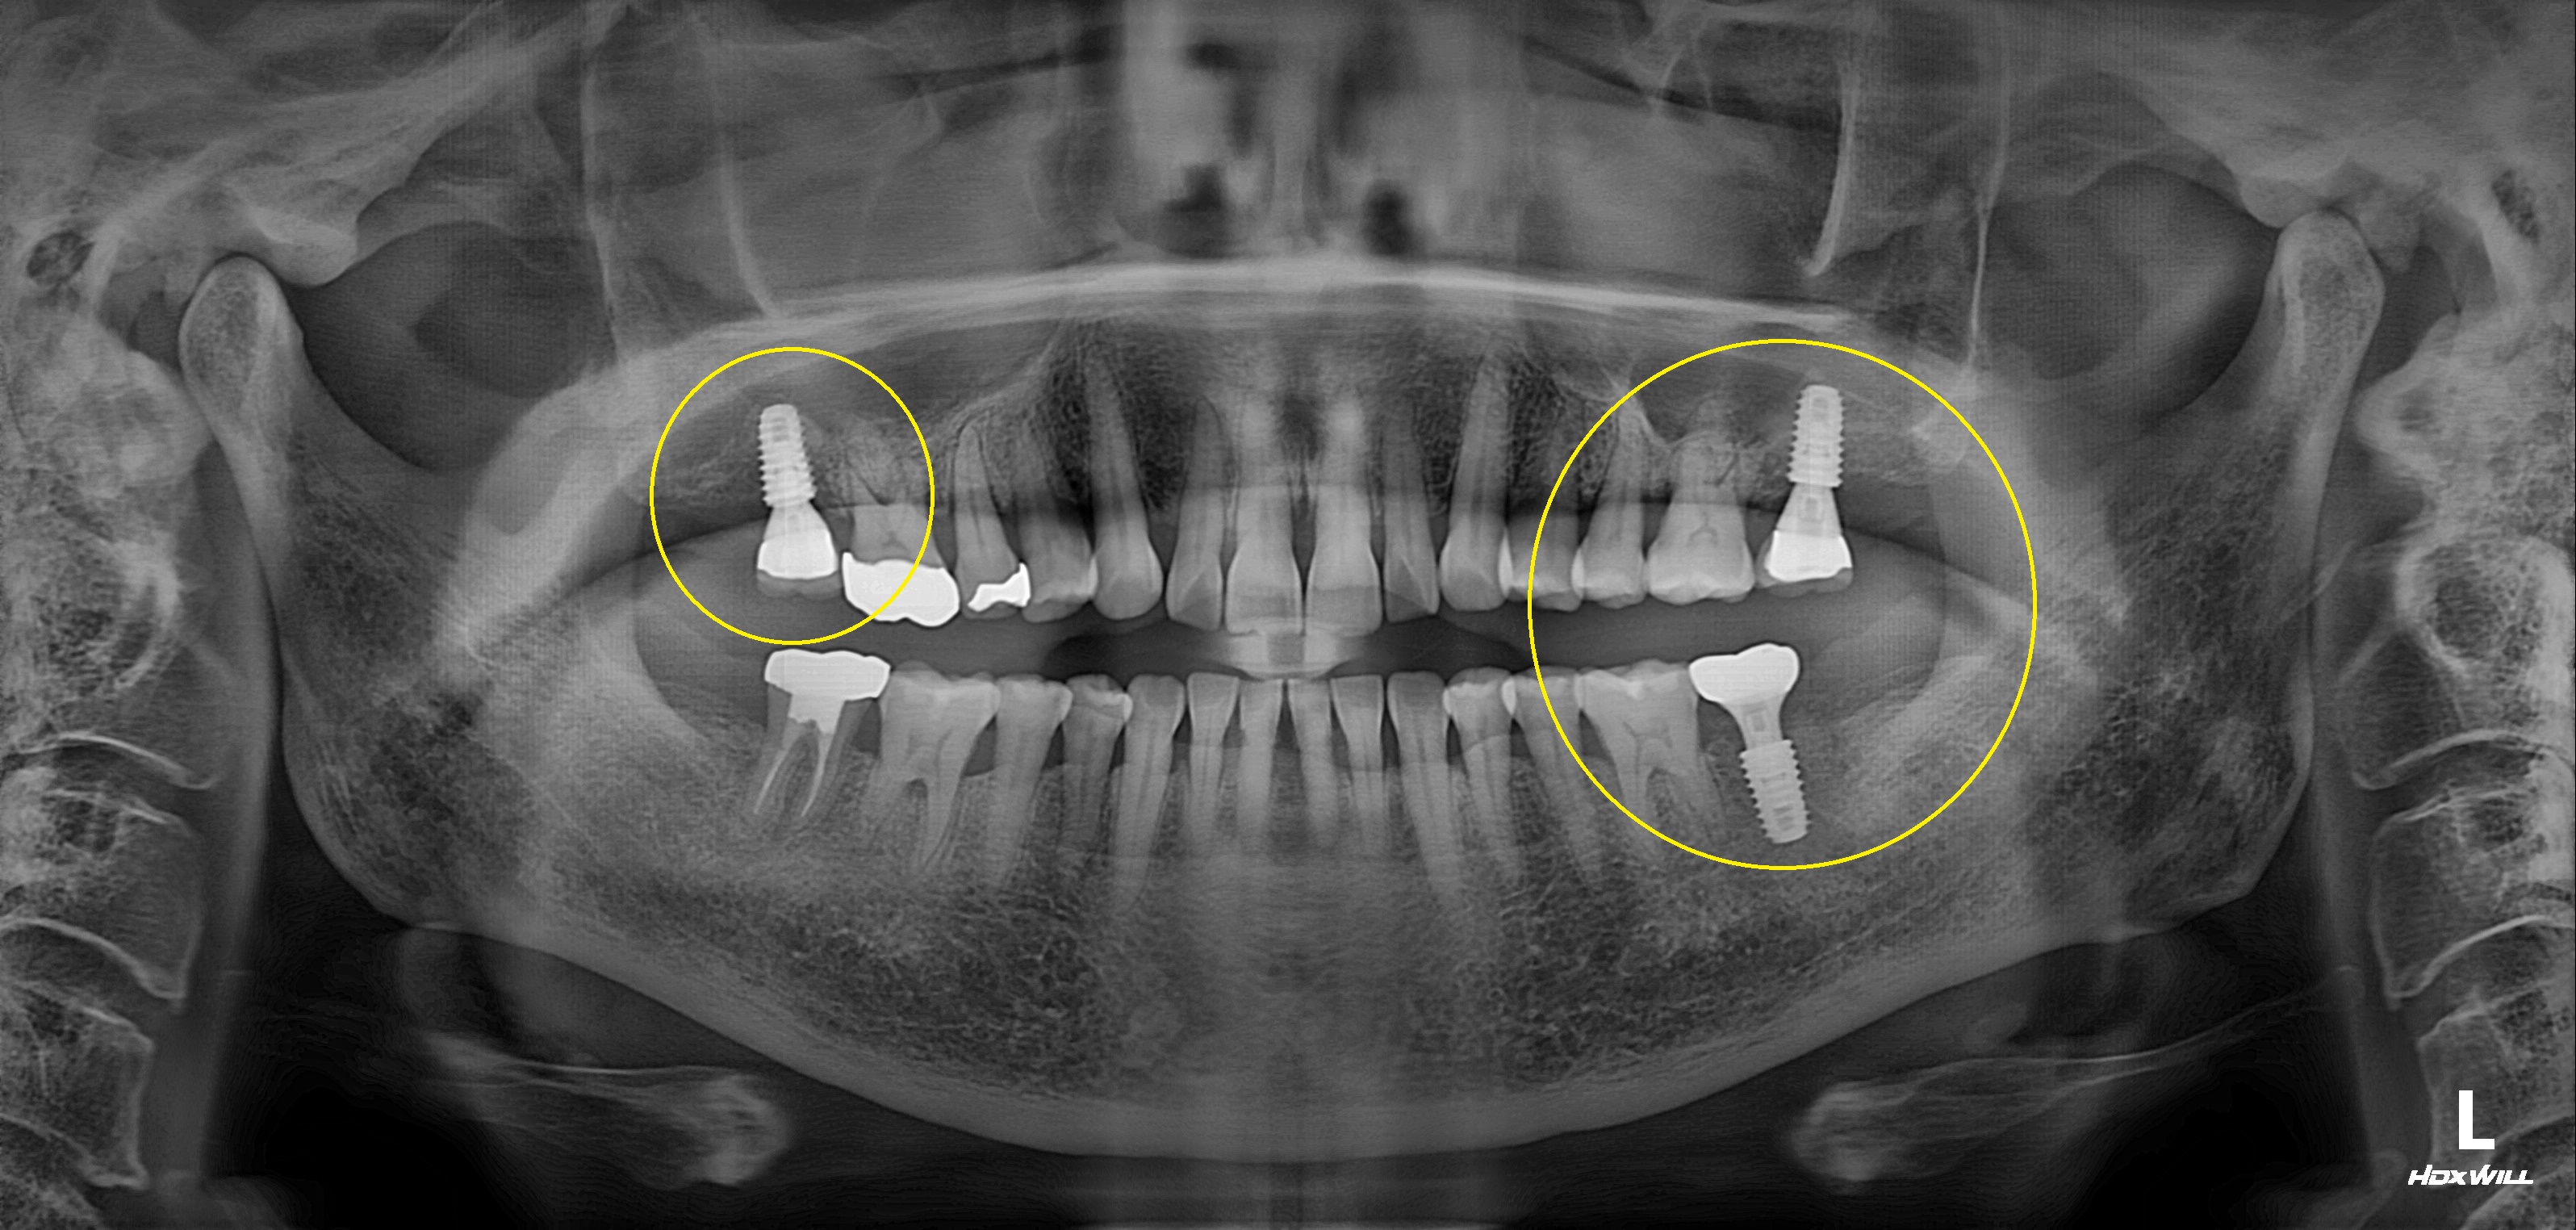

수술 전

수술 후

하악 임플란트 식립사례

전후사진